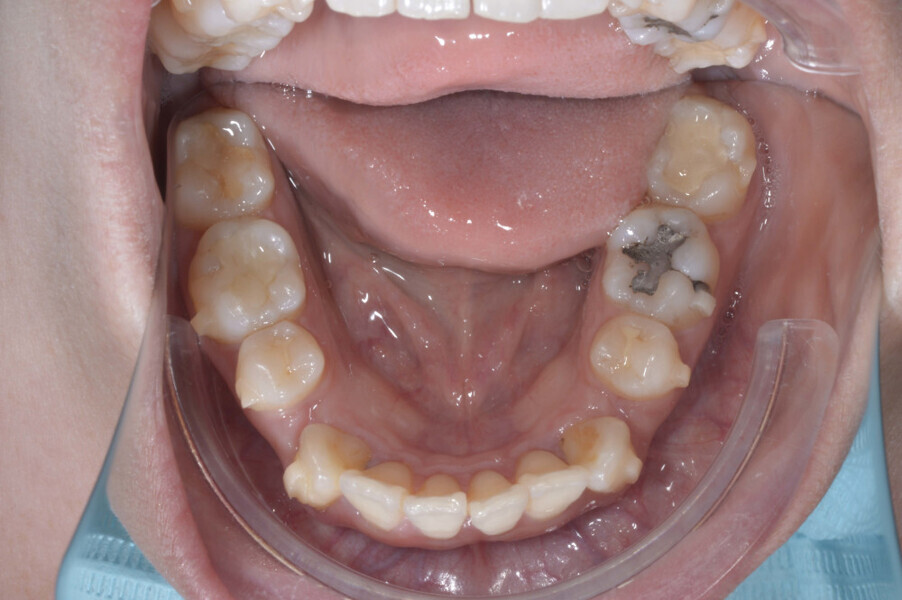

A 35-year-old female patient presented with crowding, muscle and joint pain, and headaches upon awakening. Examination found a skeletal Class I with crowding and bimaxillary protrusion. Facial examination showed a convex profile with protruded lips and a square face shape, intensified on smiling (Figs. 1–4). She reported bruxism, and bilateral masseteric hypertrophy was observed, but there was no alteration of the temporomandibular joints.

Before the aligner treatment began, the maxillary and mandibular second premolars were extracted to create space. With orthodontic treatment, distalisation of the anterior teeth was achieved by employing maximum mandibular anchorage and moderate maxillary anchorage (Figs. 5–7). At the end of the treatment, a stable bilateral Class I occlusion had been achieved, as well as normal inclination and retrusion of the anterior teeth, consequently improving the profile (Figs. 8–10).